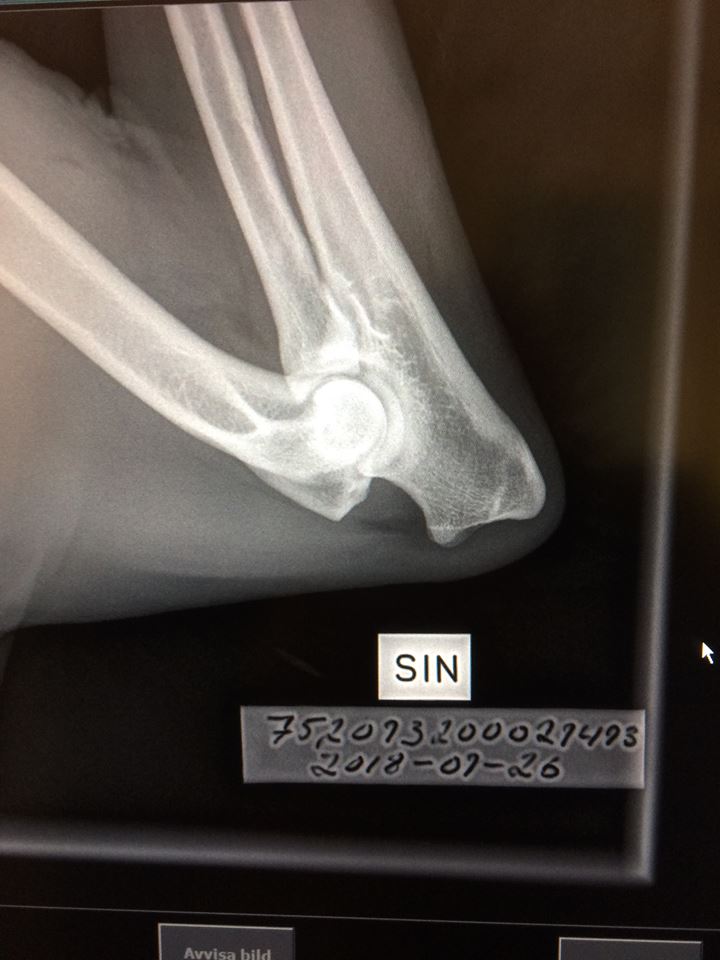

Signes vänstra armbåge avläst med 0